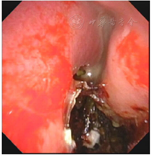

纤维鼻咽镜示双侧鼻腔较大脓血性分泌物及黑褐色干痂附着,可见鼻中隔穿孔(图2)。